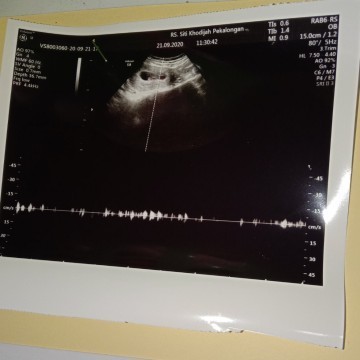

Bun saya bingung harus bagaimana? Kata dokter detak jantung janin lemah, umur kehamilan 10week..

Kemaren 9week ngeflek cuman konsul kebidan dikasih obat, trus 10week ngeflek lagi langsung keRS usg.. Detak jantung janin lemah, janin nggak gerak seharusnya udah bisa gerak2.. Saran dokter dikuret Tp saya nggak mau, nunggu seminggu dulu ada perkembangan nggak.. Menurut bunda masih ada harapan tidak? Saya harus mengkonsumsi apa saja? Apakah ada yg mengalami hal serupa? #seriusnanya #pliskasihsaranbun